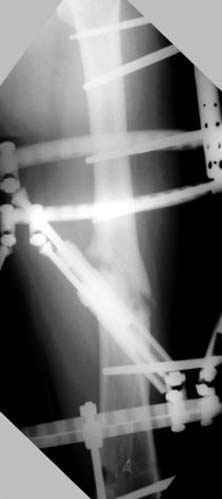

Djoldas Kuldjanov 23 Ноябрь 2004, 18:21

пластическая модель; и коррекция бедра аппаратом Илизарова.

Имею другие снимки тоже, получится как отчет о моей работе.

Отправитель: Evgueny Tschekashkin 24 Ноябрь 2004, 21:09

хотя даже если бы и инфекция , то nail exchange с рассверливанием канала - вариант дебрайдмента) Я думаю, что последовательность развития событий:

Узкий к-м канал - тонкий гвоздь- усталостный перелом дистальных винтов - развитие нестабильности и как ее результат остеолиз вокруг гвоздя - деформация анатомической оси бедра. Похоже, что я понял почему аппарат, а не новый гвоздь:-)